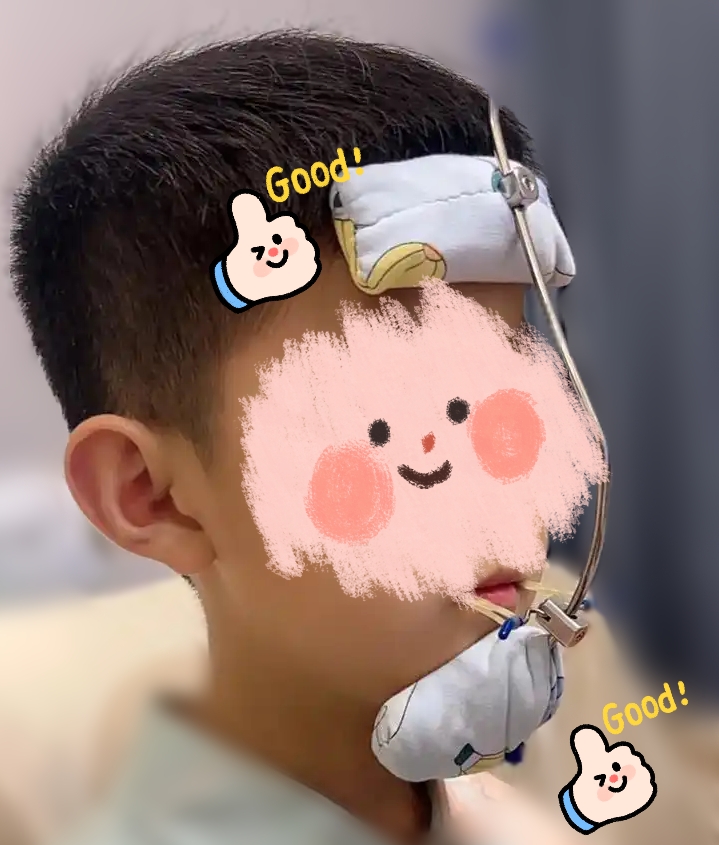

二、“面具”的真面目:矫治器的组成

这个看似复杂的装置,其实主要由两大部分组成:

2. 口外面具 - 牵引的“引擎”

面具由额垫相连颏垫组成,中间的横杆,用来挂弹力圈。

3. 牵引部件 - 力量的“传输带”

正畸弹力圈:一端挂在口内装置的拉钩上,另一端挂在口外面具的横杆上,从而将面具产生的向前牵引力精准地传递到上颌骨和牙齿上。

* 再将口外面具的额垫和颏垫放置到位。

* 最后,将弹力圈挂到口内拉钩和面具横杆上。前方牵引常用的弹力圈型号是“老虎”尺寸,一边挂2根,两边共4根,每天更换。